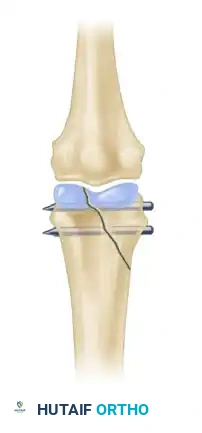

Figure 3: Two wires are strictly necessary to avoid rotation of the reduced fragment and ensure absolute stability of the articular surface.

Figure 4: Anteroposterior radiograph demonstrating a condylar fracture anatomically reduced and fixed with two crossed Kirschner wires.

Figure 5: Lateral radiograph of the same condylar fracture, confirming restoration of the articular contour and appropriate wire placement.